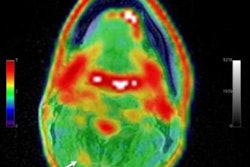

Average SUV ratio PET images of stroke rat model over time as compared with a sham rat using mean cerebellum as the reference. Image courtesy of T. Toyonaga and X. Lyu, Yale University, New Haven CT.The new imaging method enabled the researchers to successfully detect synapse loss in the rats. The loss of synapses was most evident in the hippocampus, thalamus, and neocortex, but not the cerebellum.